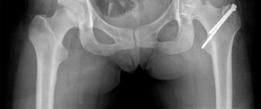

Standard preoperative imaging must include an anteroposterior (AP) pelvis, cross-table lateral, and false-profile view of the affected hip. These evaluate for dysplasia, impingement morphology (cam/pincer), and degenerative changes.

Magnetic Resonance Arthrography (MRA) is the gold standard for evaluating the capsuloligamentous complex. Extravasation of contrast anteriorly often delineates the size and location of the capsular defect. MRA also assesses labral integrity, chondral damage, and the viability of the femoral head. A 3D computed tomography (CT) scan is highly recommended to quantify femoral anteversion and acetabular version, as unrecognized osseous malorientation (e.g., severe femoral retroversion) will predispose the reconstruction to failure if not addressed concurrently with a derotational osteotomy.